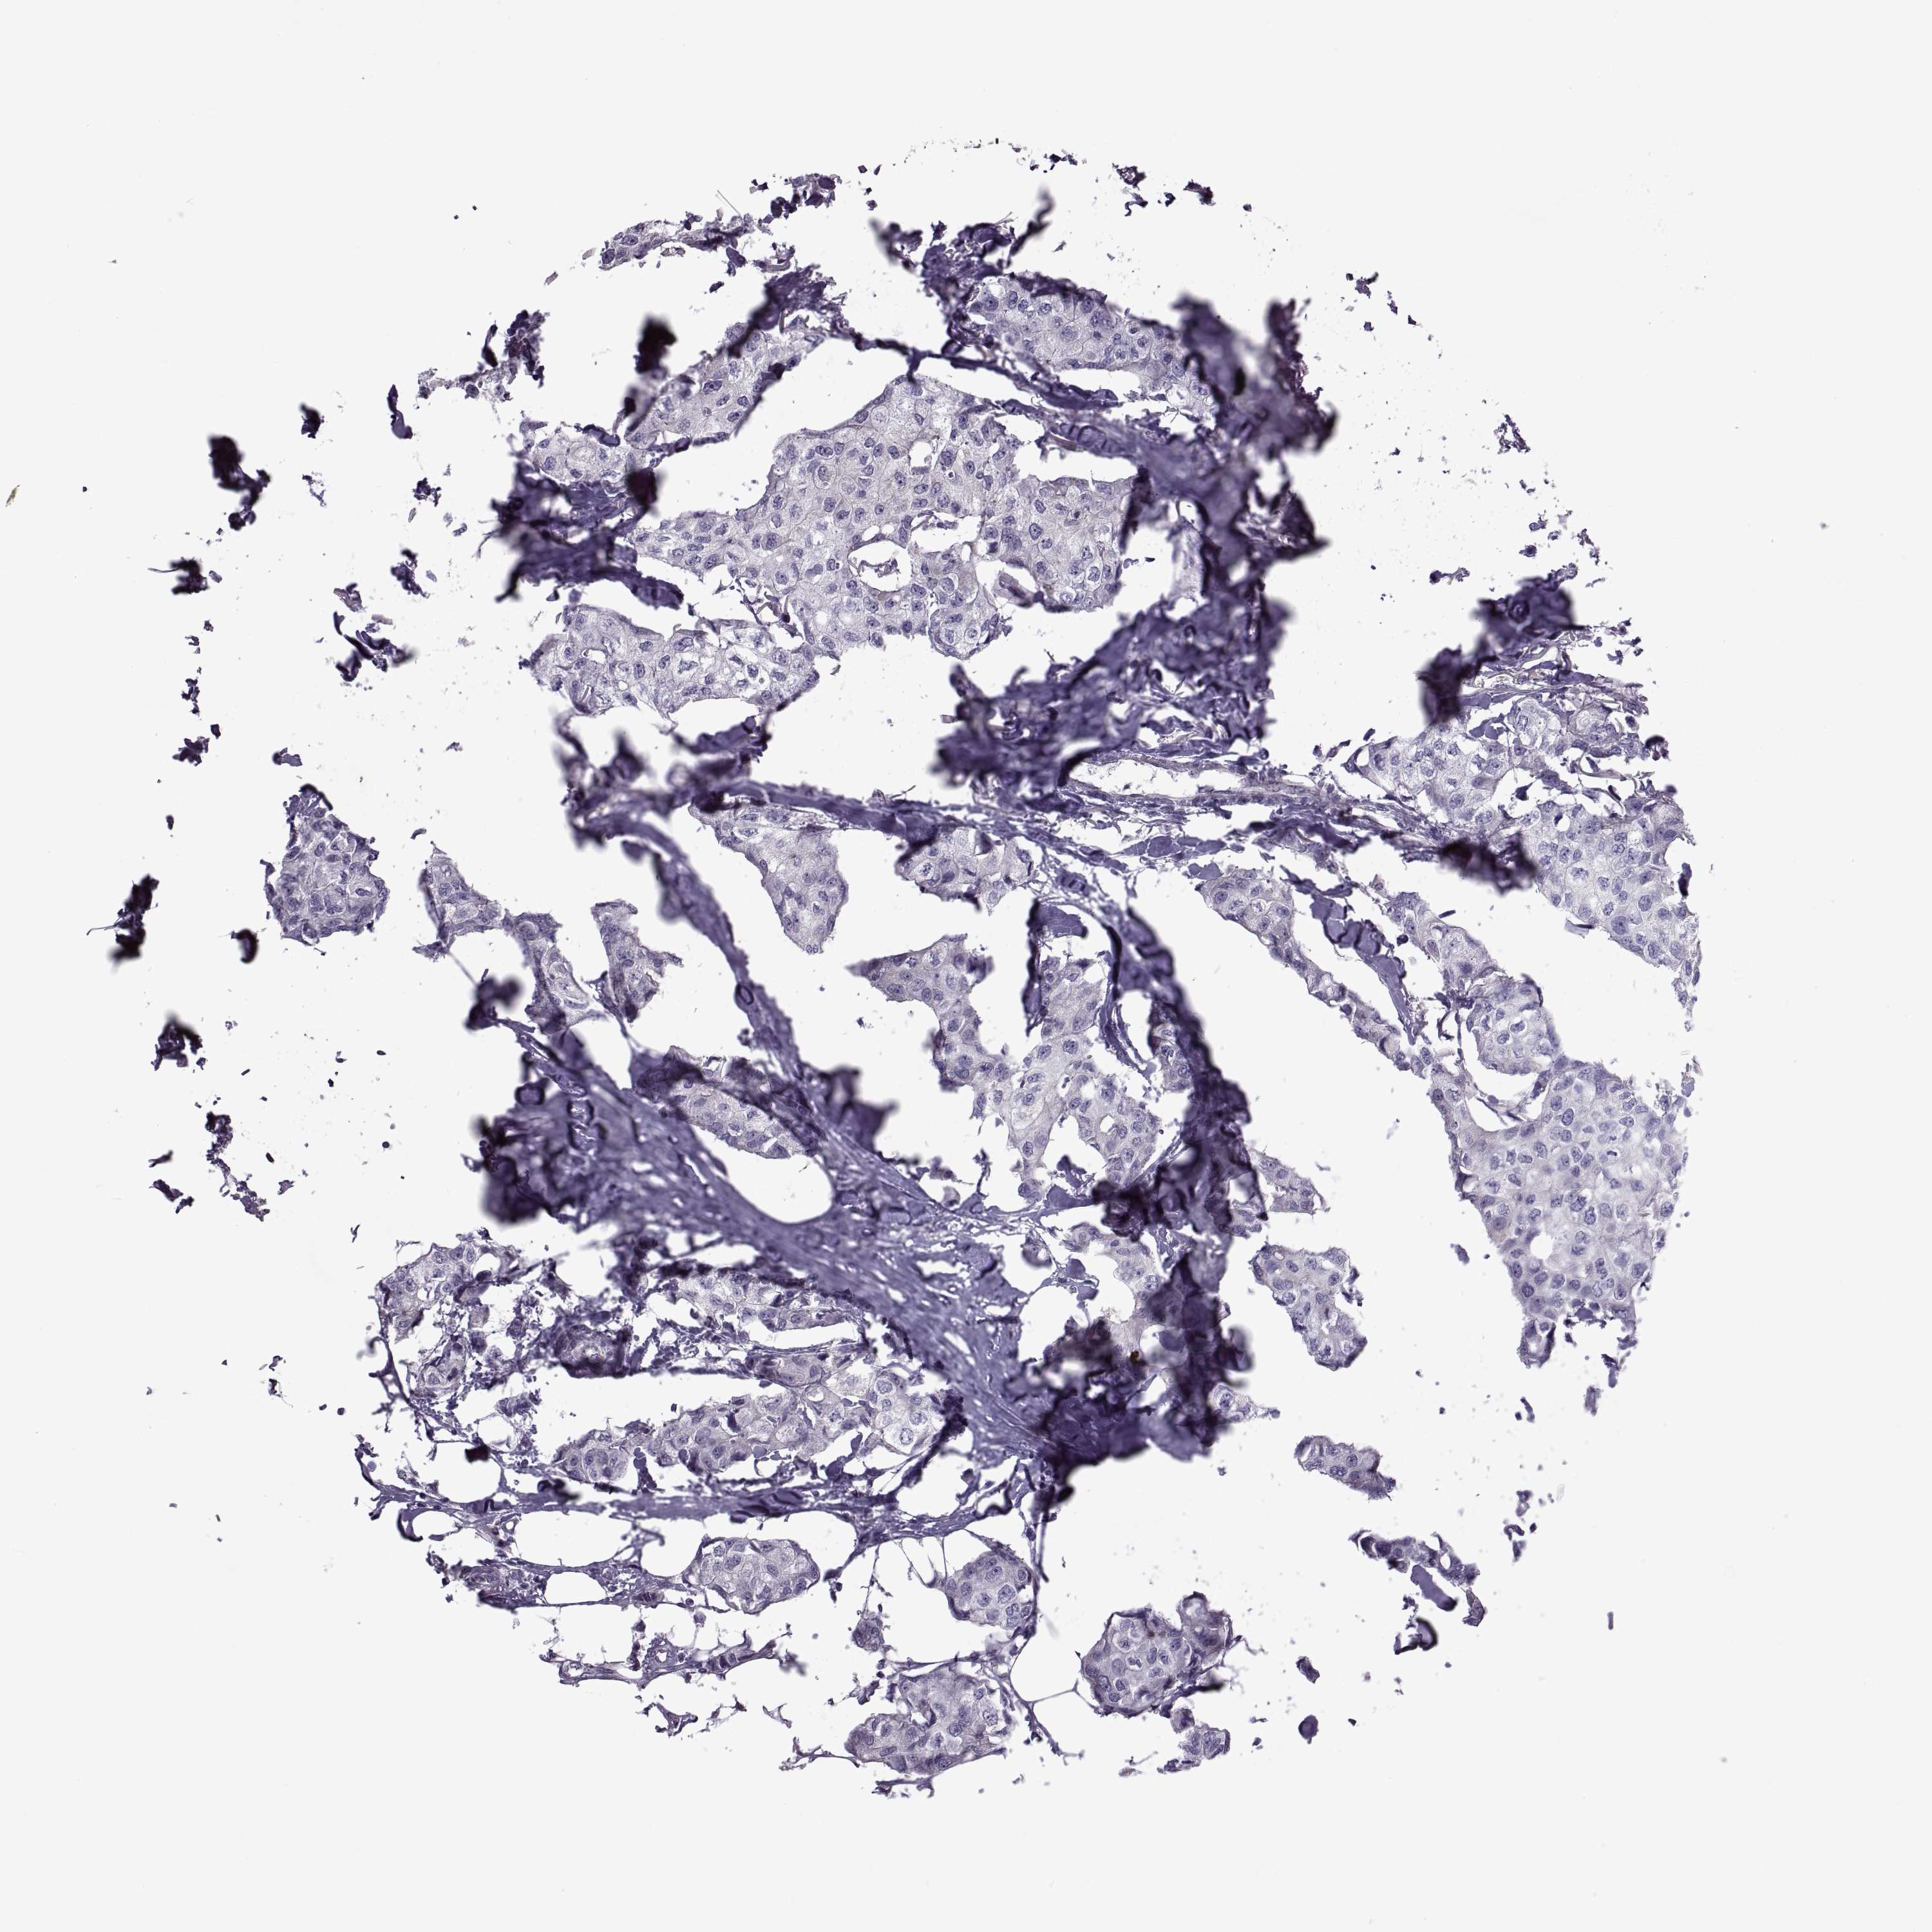

BRCA TCGA BRCA VALIDATION PROTEIN EXPRESSION